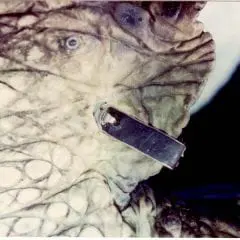

2012- Photo Depictions of Auto-Grafting a Juvenile Green Turtle.